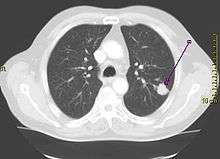

| A chest X-ray showing a tumor in the lung (marked by arrow) | |

The vast majority (85%) of cases of lung cancer are due to long-term tobacco smoking.[7] About 10–15% of cases occur in people who have never smoked.[8] These cases are often caused by a combination of genetic factors and exposure to radon gas, asbestos, second-hand smoke, or other forms of air pollution.[9][7][10][11] Lung cancer may be seen on chest radiographs and computed tomography (CT) scans.[1] The diagnosis is confirmed by biopsy which is usually performed by bronchoscopy or CT-guidance.[12][13]

Performing a chest radiograph is one of the first investigative steps if a person reports symptoms that may suggest lung cancer. This may reveal an obvious mass, widening of the mediastinum (suggestive of spread to lymph nodes there), atelectasis (collapse), consolidation (pneumonia) or pleural effusion.[1] CT imaging is typically used to provide more information about the type and extent of disease. Bronchoscopy or CT-guided biopsy is often used to sample the tumor for histopathology.[13]

Lung cancer often appears as a solitary pulmonary nodule on a chest radiograph. However, the differential diagnosis is wide. Many other diseases can also give this appearance, including metastatic cancer, hamartomas, and infectious granulomas such as tuberculosis, histoplasmosis and coccidioidomycosis.[61] Lung cancer can also be an incidental finding, as a solitary pulmonary nodule on a chest radiograph or CT scan done for an unrelated reason.[62] The definitive diagnosis of lung cancer is based on histological examination of the suspicious tissue[6] in the context of the clinical and radiological features.[12]